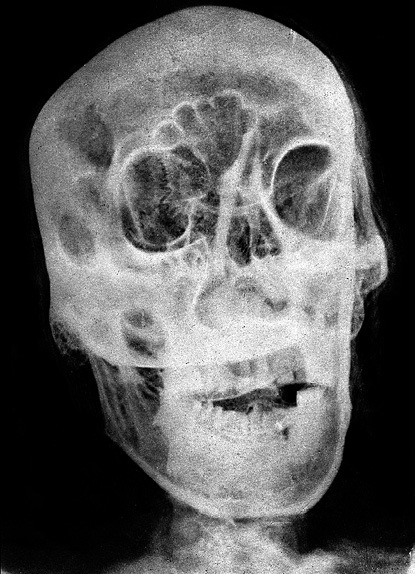

Илл. 2. Рентгенологическое исследование мумии (по Михайловскому)

Его извлекали, как пишет Геродот, «через ноздри», а в реальности, вероятно, проламывая concha nasalis superior, os lacrimale, proc. uncinatus, т. е. верхнюю носовую раковину, слезную кость и крючковидный отросток (Михайловский В. Г. Опыт рентгенологического исследования египетских мумий. СМАЭ, 1928. Т. 8) (Илл. 2).